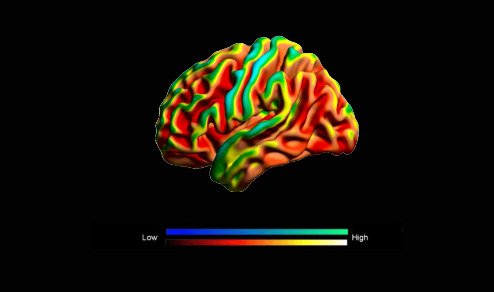

Este año, los científicos han descubierto que al ‘alternar’ las frecuencias en un patrón fractal, se consigue emular el ciclo de la naturaleza al crear nuevas conexiones neuronales, estimulando con éxito la corteza prefrontal.

Mediante una fusión de los efectos de sincronización hemisferial y neuronal.

Sincronización Hemisferial + Neuronal = Activación Prefrontal

Resultado: Capacidad de Cognición Optimizada

Tecnología Interaural de Sincronización Hemisferial

Conecta Ambos Hemisferios

La primera capa de la tecnología HybridWave™ potencia este fenómeno.

Gracias a su tecnología de diferencia interaural, se logra sincronización hemisferial.

Sincronizando tus ondas cerebrales entre hemisferios para liberar tu máximo potencial cognitivo.

Como Da Vinci, puedes activar la intuición del hemisferio derecho y la lógica del izquierdo en perfecta armonía, accediendo a una inteligencia más profunda y multidimensional.